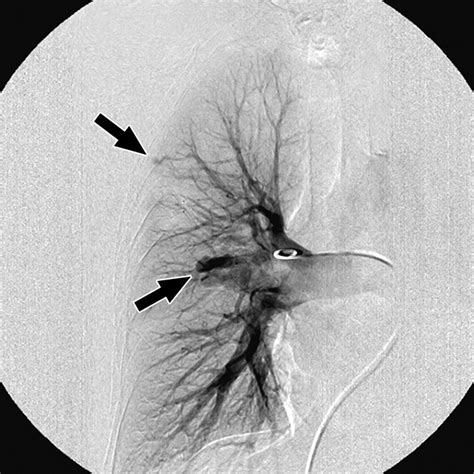

Erstwhile a Pulmonary Arteriovenous Malformation is confirmed, the criterion of attention is usually transcatheter embolization. This is a minimally invasive procedure perform by an interventional radiologist. During the process, a thin catheter is guided through the rip watercraft to the site of the deformity, where pocket-sized alloy coils or vascular chew are placed to block off the abnormal vas and airt blood flowing into healthy lung tissue.

Post-treatment follow-up is indispensable. Even after successful embolization, doctors recommend periodical imagery to control that the PAVM has not reopened or that new, smaller malformations have not germinate.